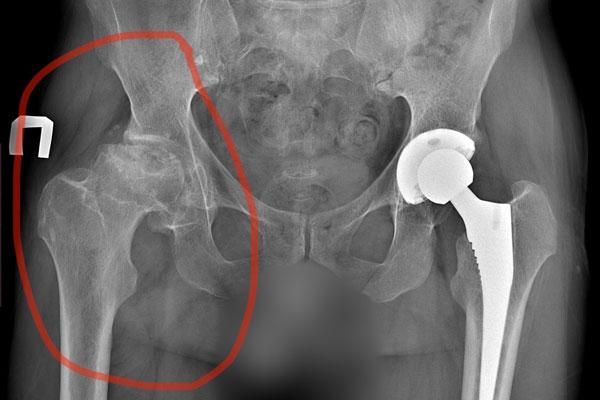

Если у Вас установлен диагноз коксартроза 3-4 стадии, есть нарушение нормальной функции тазобедренного сустава и снижено качество Вашей жизни, то решением проблемы является замена тазобедренного сустава.

Эта операция заключается в удалении пораженных частей тазобедренного сустава - головки бедра и суставной впадины, и установки искусственных качественных компонентов с идеально подобранными характеристиками. При правильной установке компонентов искусственного сустава человек получает возможность БЕЗболезненного движения в течение длительного времени